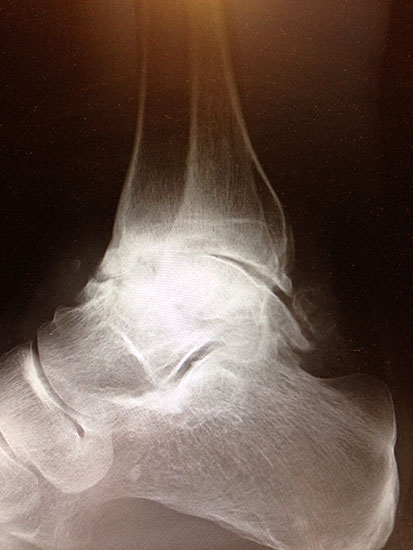

Erreichen eines schmerzfreien oberen Sprunggelenkes mit belastbarem und plantigrad aufsetzbarem Fuss (Abb. 1a und b) unter Verzicht auf die Bewegungsfunktion des oberen Sprunggelenkes. Operative Resektion der arthrotisch veränderten Gelenkflächen bis in den subchondralen frischen Knochen von Tibia und Talus. Fusion mittels Kompressionsschrauben oder Arthrodeseplatten, bedarfsweise Arthrodesenagel.

Abbildung 1a